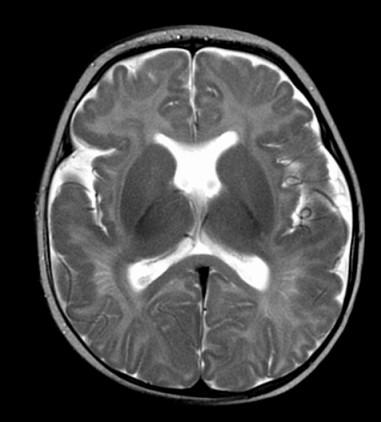

Differential for “cyst in the posterior fossa” starts with whether the vermis is normal or not.

Is the vermis normal? Can you identify the normal structures of the Vermis?

Malrotated hypoplastic vermis, with vertical primary fissure.

“OPEN” fastigial point of the fourth ventricle. Hypoplastic cerebellar hemispheres.

Enlarged posterior fossa

Cystic dilatation 4th ventricle

Uplifted tentorium, TSV sinus, torcula

“torcula-lambdoid inversion” with torcula above the lambdoid suture

Agenetic or hypogenetic vermis with “vermian tail, pushed upward

Cerebellar hypoplasia

CC anomalies 32%

Hydrocephalus up to 90%

Aqueductal stenosis

4th ventricle outlet obstruction

Polymicrogyria, heteropia 5-10%

Occipital Meningo-Encephaloceles 16%

Syndromic = Extracranial anomalies 50%